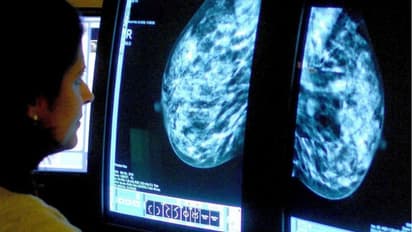

സ്ത്രീകള്ക്കിടയില് ഏറ്റവുമധികം കണ്ടുവരുന്ന അര്ബുദമാണ് സ്തനാര്ബുദം. സമയത്ത് കണ്ടെത്താത്തതിനാലും, ചികിത്സ തേടാത്തതിനാലും സ്തനാര്ബുദം ബാധിച്ച് മരണപ്പെടുന്ന സ്ത്രീകളുടെ എണ്ണം ആഗോളതലത്തില് തന്നെ ഓരോ വര്ഷവും ഉയരുകയാണ്. ഇതിനിടെയാണ് ചരിത്രപരമായ കണ്ടെത്തലെന്ന അവകാശവാദവുമായി ഒരുകൂട്ടം ഗവേഷകര് രംഗത്തെത്തിയിരിക്കുന്നത്.

സ്തനാര്ബുദത്തില്ത്തന്നെ ഏറ്റവും അപകടകാരിയായ 'ട്രിപ്പിള് നെഗറ്റീവ് ബ്രെസ്റ്റ് ക്യാന്സര്' ഉള്ള സ്ത്രീകളില് നടത്തിയ പരീക്ഷണത്തിന്റെ അടിസ്ഥാനത്തിലാണ് ലണ്ടനിലെ ഗവേഷകര് പുതിയ കണ്ടെത്തലിനെ കുറിച്ച് വെളിപ്പെടുത്തിയിരിക്കുന്നത്. അതായത്, സ്തനാര്ബുദത്തെ പ്രതിരോധിക്കാനും ഇതിനെതിരെ പോരാടി രോഗം തുടച്ചുമാറ്റാനുമെല്ലാം കഴിവുള്ള ഒരിനം കോശം മനുഷ്യരുടെ ബ്രെസ്റ്റ് ടിഷ്യൂവില് കണ്ടെത്തിയെന്നാണ് ഇവര് പറയുന്നത്.